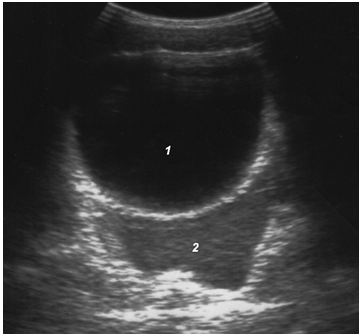

Эхографическая визуализация жидкости только в полости малого таза соответствует «малому» гемоперитонеуму, объем крови при этом не превышает 7,3 мл/кг массы тела (рис. 11).

Рис. 11. «Малый» гемоперитонеум: 1 – мочевой пузырь; 2 – кровь.